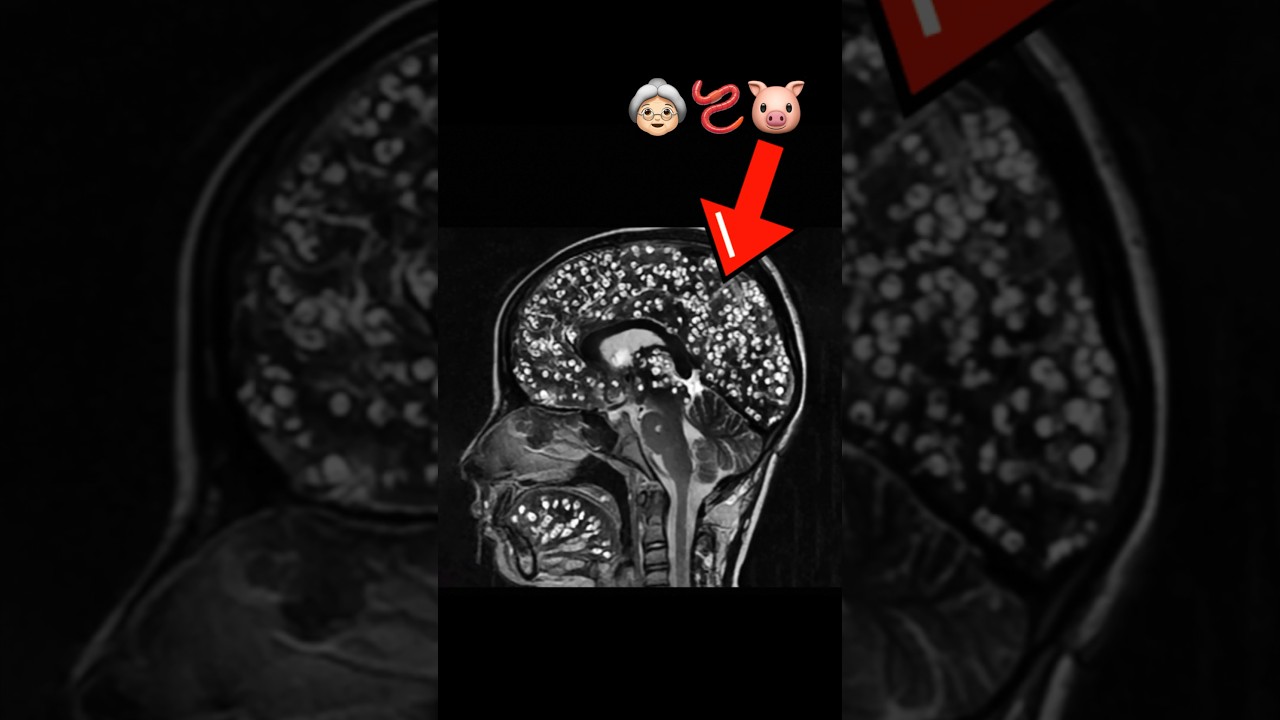

Мозг бабушки был заражен ленточными червями. Вот что произошло дальше… #медицина #паразит